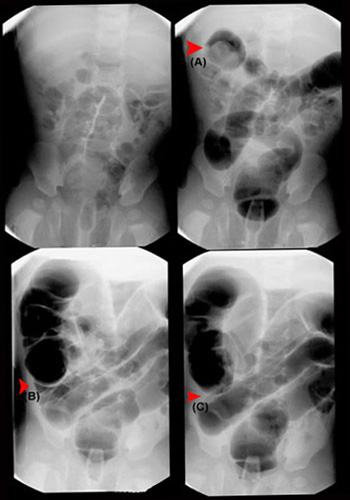

Air enema (clockwise from upper left):

• Pre-reduction scout film

• Demonstration of intussusception in hepatic flexure (A)

• Reduced to ileocecal valve (B)

• Completely reduced with air refluxed into small bowel (C)